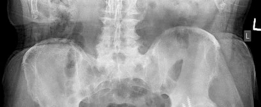

For anyone wondering about Acetabular Revision: Solving Challenges Post Two-Stage Arthroplasty, A **title acetabular revision** is a complex procedure addressing issues like septic loosening, dislocation, and significant osteolysis in total hip arthroplasty. For a 71-year-old male with a dislocated left THA due to infection and periacetabular bone loss, treatment involved a two-stage exchange followed by revision with a press-fit hemispherical cup and screw fixation.

Standard anteroposterior pelvis and cross-table lateral radiographs are mandatory. Judet views (iliac and obturator obliques) are critical for assessing the integrity of the anterior and posterior columns. However, plain radiography often underestimates the extent of osteolysis and bone loss.

High-resolution Computed Tomography with Metal Artifact Reduction Sequence is essential for three-dimensional evaluation of the remaining bone stock. Computed Tomography allows for the definitive diagnosis of pelvic discontinuity, the assessment of the medial wall, and the quantification of ischial and iliac bone available for fixation.